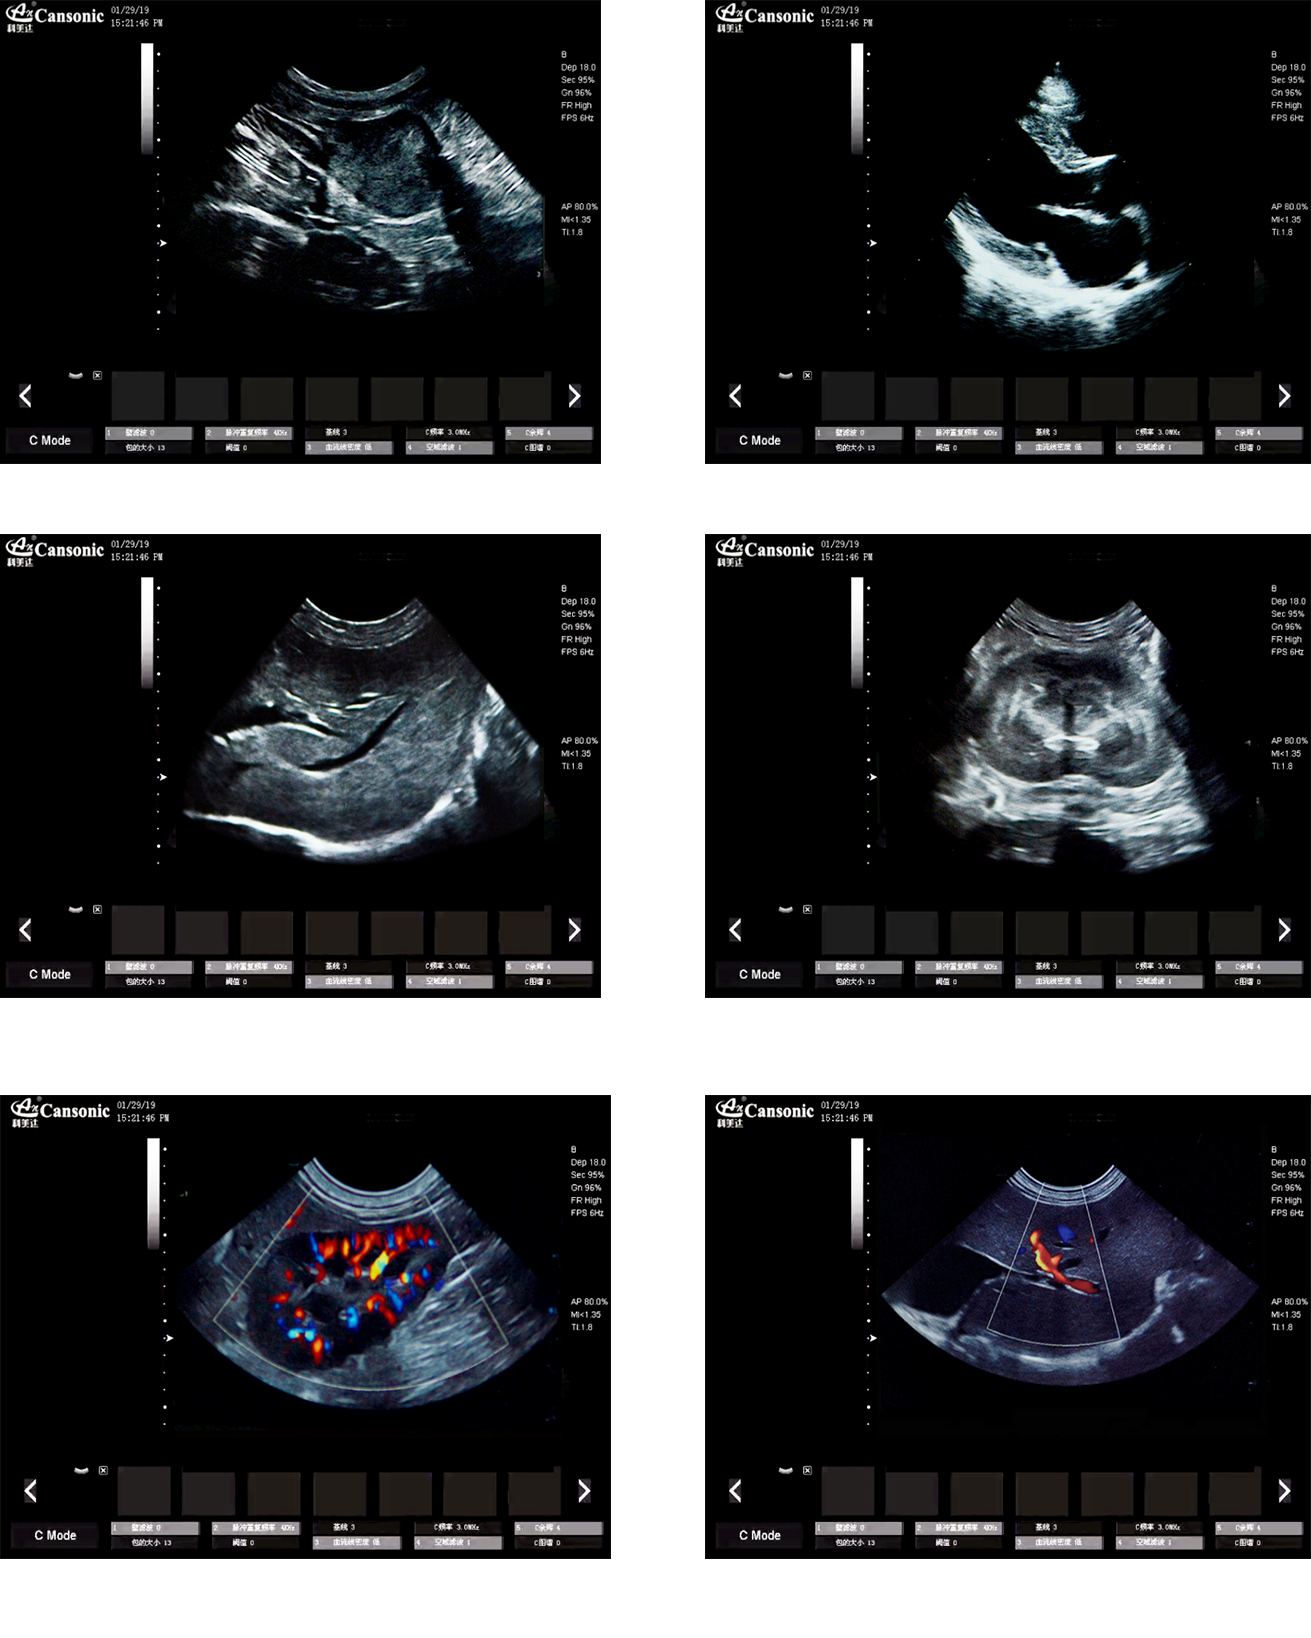

1、薈萃高端彩超的專業(yè)技術,各類型的專業(yè)獸用探頭,提供完整的動物臨床診療方案

2、專業(yè)的獸用彩超軟件,適合犬、貓、馬、牛、羊等各類大小動物彩超檢查

3、完備的獸用高端功能,能量多普勒POWER模式彩色多普勒Color成像模式

4、精準全數字濾波技術,有效降低多普勒噪聲及運動偽像,提升多普勒超聲圖像

臨床圖示